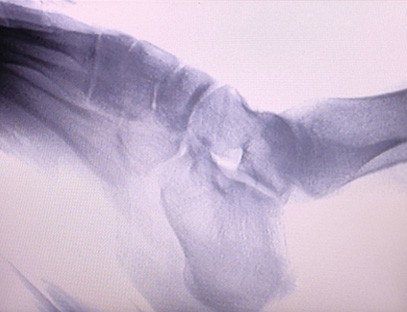

Ixtisosligi:Ortopediya klinikalari ehtiyojlari uchun mo'ljallangan, ayniqsa mos keladiRentgen tasviriqo'llar, bilaklar, tirsaklar, yelkalar, tizzalar, to'piqlar va boshqalar kabi a'zolarning.

Aniq tasvir:Yuqori sifatli rentgen tasvirlarini taqdim etish uchun ilg'or raqamli tasvirlash texnologiyasi qo'llaniladi, bu shifokorlarga kasallikni aniq tashxislashda yordam beradi.